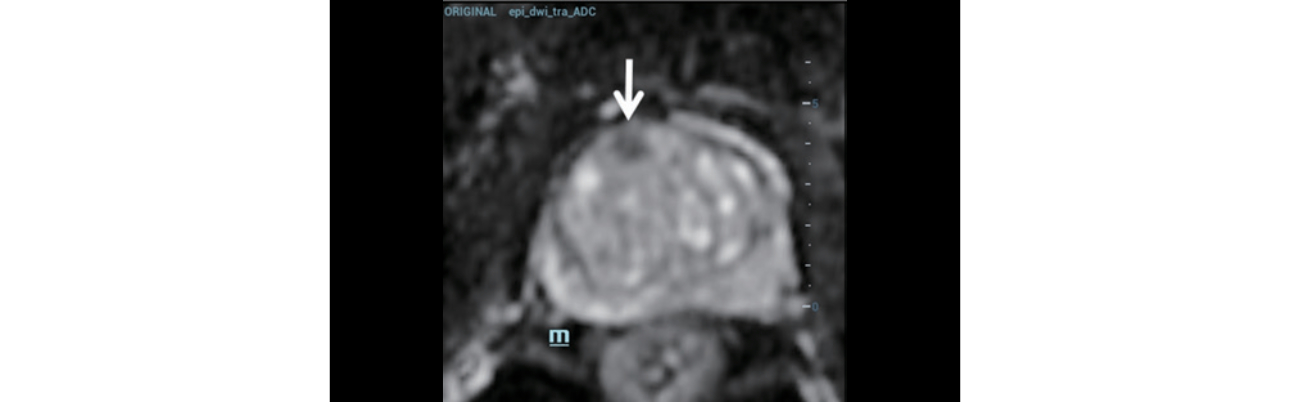

Step 1: The appropriate MRI sequence (Figure 2) was selected and the dataset imported onto the Resona 9 and into the live ultrasound exam.

Step 2:?Using MindrayŌĆÖs iFusion software, the TRUS and MRI images were aligned and fused (Figure 3) and the target was labeled (Figure 4).

Step 3:?To verify the lesion location, a contrast enhanced ultrasound (CEUS) was performed using the MRI image for anatomical reference (Figure 5).

Systemic biopsy is the current main diagnostic method for PCa. As the biopsy sites are standardized rather than targeted at a particular suspicious lesion, this method may also result in missed diagnosis or underestimation of disease. Multi parameter MRI has a high sensitivity and specificity for the diagnosis of PCa, however, MRI guided biopsy is complicated and expensive. Mindray iFusion software on the Resona 9 provides a solution by fusing the MRI dataset with live ultrasound imaging. Using bi-plane TRUS/MRI fusion guidance for targeted prostate biopsy improves the accuracy of clinical prostate cancer diagnosis [2].

In this case, the suspicious lesion was detected on MRI and using iFusion navigation the corresponding plane and target area were labeled on ultrasound. A CEUS exam provided additional diagnostic information and three guided biopsies were performed into the suspect area. While the standard 12-point samples were negative, one of the targeted samples came back positive for PCa. This case clearly shows how biplane TRUS/MRI fusion targeted biopsy can help avoid missed diagnosis and improve diagnostic accuracy.